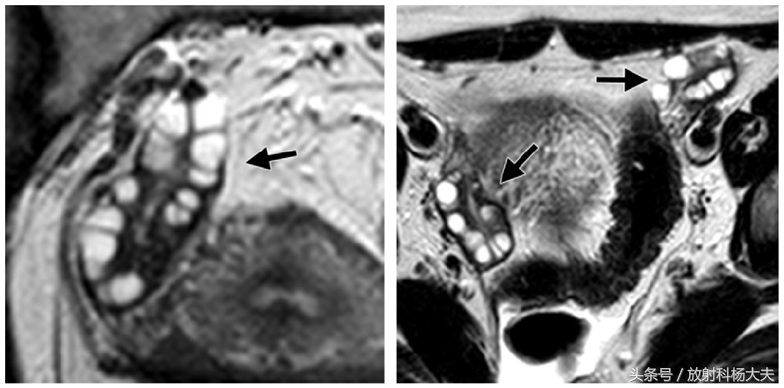

MRI属于无创检查,做过MRI的朋友都知道,患者只需要在那躺着,各项检查就这么神不知鬼不觉的完成了。而且MRI对人体没有任何电离辐射,这点尤其适合那些年轻的或者想生育的女性朋友们。MRI对软策划有极好的分辨率,可以通过多参数成像提供丰富的诊断信息,而且可以通过多角度成像选择各种剖面,获得其他成像技术所不能或难以获得角度的图像。卵巢是位于子宫两侧的一对卵圆形的生殖器官。正常卵巢信号在 T1WI上为均匀的中等或稍低信号强度,内部结构不易分辨。T2WI序列表现为多个大小不一的小圆形或小卵圆形的,均匀高信号囊性结构,囊内信号与液体一致,位于卵巢皮质内,典型呈花环样排列,以T2WI压脂序列显示最清晰。囊壁在 T1WI表现为等信号,T2WI囊壁较T1WI显示清晰,呈均匀的等低信号。在生育年龄妇女,卵巢髓质内含有大量富含血管的疏松结缔策划,T2WI上也表现为稍高信号。正常女性单侧卵巢卵泡数目6~7个,一般不超过10个,正常卵巢体积约6~7 cm3大小。在排卵期,优势卵泡的直径最大可达2 cm。多囊卵巢综合症患者的卵巢 MRI信号与正常卵巢一致,而卵巢体积较正常卵巢增大,卵泡数目较正常增多,卵泡排列无特别规律,可沿周边分布,亦可弥漫分布。与正常女性相比,多囊卵巢综合症患者双侧卵巢较正常卵巢增大2~3倍,卵巢内可见许多闭锁卵泡和处于不同发育期的卵泡,但无成熟卵泡生成及排卵迹象。